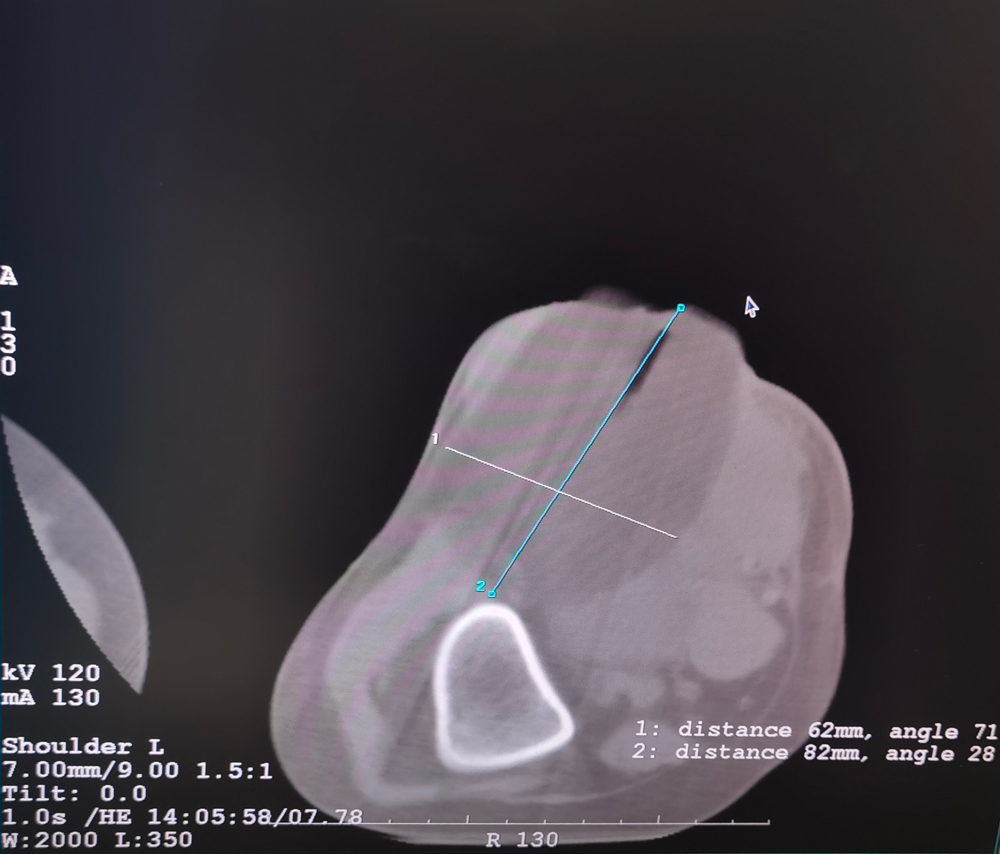

患者二

女,42岁,复发性脂肪瘤,病灶位于右侧膝关节,直径大小13cm。采用双针方案,共进行6个冻融循环,最大冰球直径达8.2cm,术中多方位治疗全面覆盖病灶范围。患者术后状况良好。